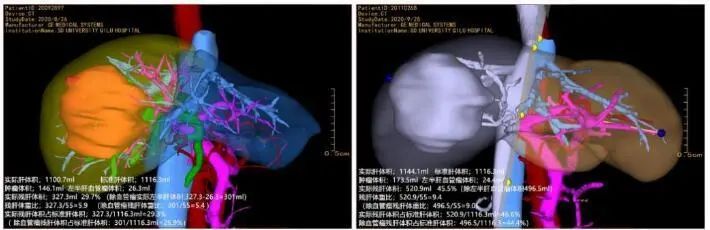

术前三维重建影像

高大伯办理住院手续、进一步检查后,张主任团队精确的计算出他剩余左肝体积至少需要410ml,也就是说患者的肝脏至少需要增加200ml,才可以实施手术。

经过3周的休养,高大伯再次住院,经复查CT和三维重建,张宇华发现老高的剩余肝脏体积增加到了510ml,也就是说完全达到了手术的要求。